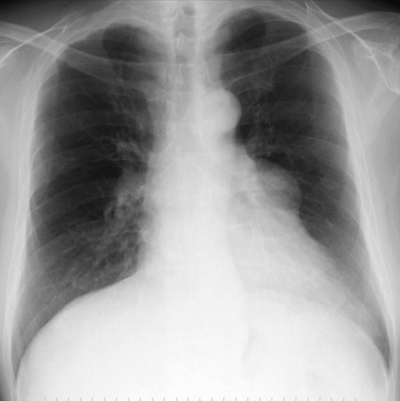

52歳の男性。脱力を主訴に来院した。3か月前から、帰宅時に駅の階段を途中で休まずには昇れなくなったため受診した。血液検査で抗アセチルコリン受容体抗体が陽性であった。胸部エックス線写真及び胸部造影 CT を別に示す。

この患者で検索すべき合併症はどれか。2つ選べ。